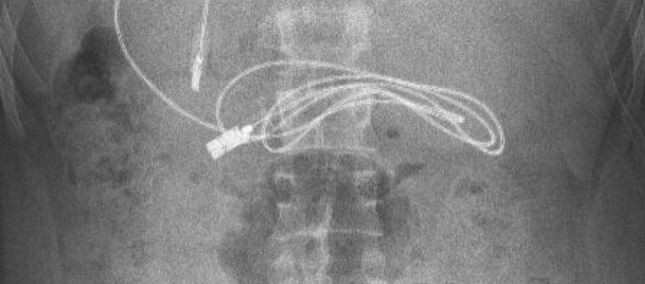

Brenda stomakut të një 15-vjeçari u gjet një kabllo të adapterit të telefonit.

Siç raportojnë mediat, kablloja ishte e gjatë një metër dhe se ishte e lidhur në nyje dhe kjo ua bëri mjekëve më të vështirë heqjen e tij.